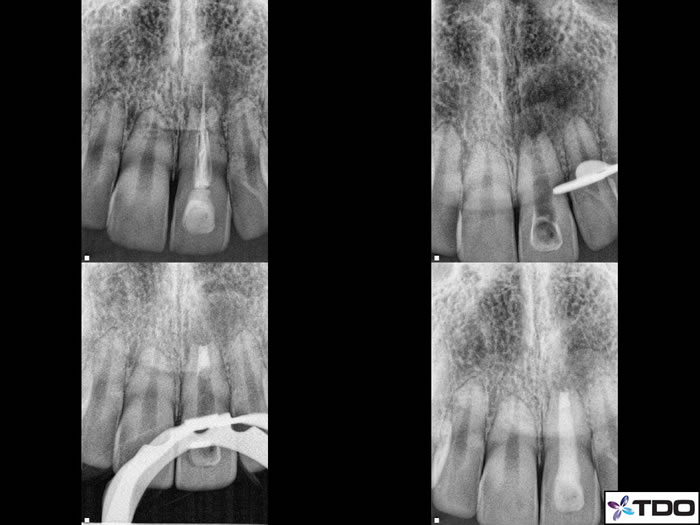

Figure 8: Root end resorption on a necrotic case. Following proper canal disinfection I packed MTA in the apical 4mm (red arrows). I then placed gutta percha in the rest of the canal and sealed coronally with composite.

Figure 7: Here is a case of Dr Monroe in which he had to perform RCT on an immature apex. The distal root is far too open to place gutta percha and thus he filled the entire distal root with MTA (red arrows).